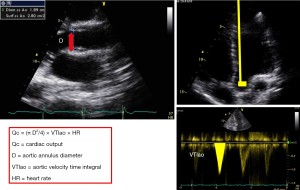

Cardiac output (Qc)

Qc is calculated as follow Qc = SV × HR where SV = CSAao × VTIao (SV is stroke volume, HR heart rate, CSAao left ventricular outflow tract (LVOT) cross sectional area, VTIao velocity time integral of LVOT) (Figure 4) (17). CSA is derived from the LVOT diameter measured from parasternal long axis view and VTIao measured on aortic blood flow recorded from apical 5-chambre view using pulsed Doppler. TTE and TEE approach could be used but small errors in diameter measurement become large errors in cross sectional area calculations because of the quadratic relationship between these variables [CSAao = (2 × 3. 14 × LVOT2)/4]. Diameter and VTI measurements be made at the same anatomic site, with an average of 3 measurements. Because LVOT size do not change any change of SV could be tracked by VTIao change. pulmonary or aortic orifice, using TTE or TEE (17-19) VSports app下载. This method was extensively validated against thermodilution in cardiologic field and in ICUs (17,20,21). Stroke volume may also be calculated as the difference of LV volume in diastole minus LV volume in systole (using the Simpson method) but this approach seems to be less accurate that previous one (22).